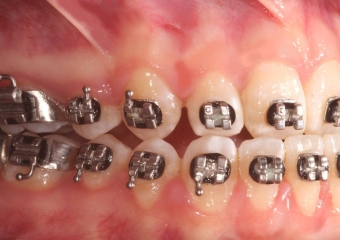

Mordida inicial

Mordida após a cirurgia